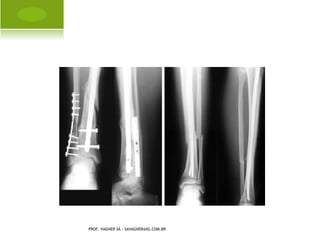

C OLLES

PROF. VAGNER SÁ - SAVAGNER@IG.COM.BR